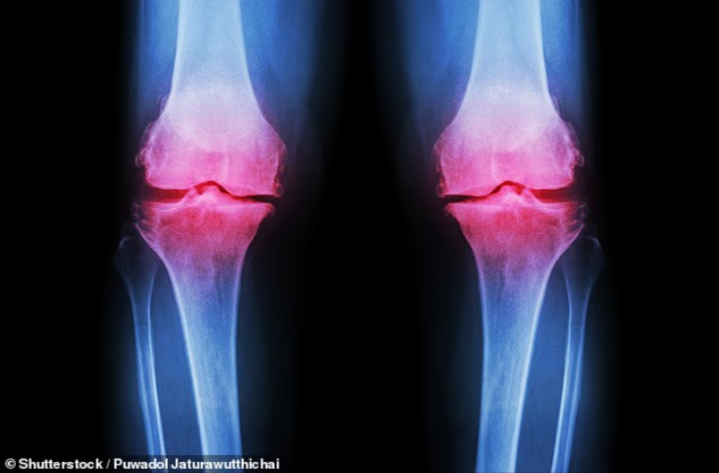

هشاشة العظام.. خطر صامت

وتتطور هشاشة العظام ببطء على مدار سنوات، وغالبًا لا يتم اكتشافها إلا بعد حدوث كسر نتيجة سقوط بسيط. وتكون النساء أكثر عرضة للإصابة، خاصة بعد انقطاع الطمث بسبب الانخفاض السريع في كثافة العظام.